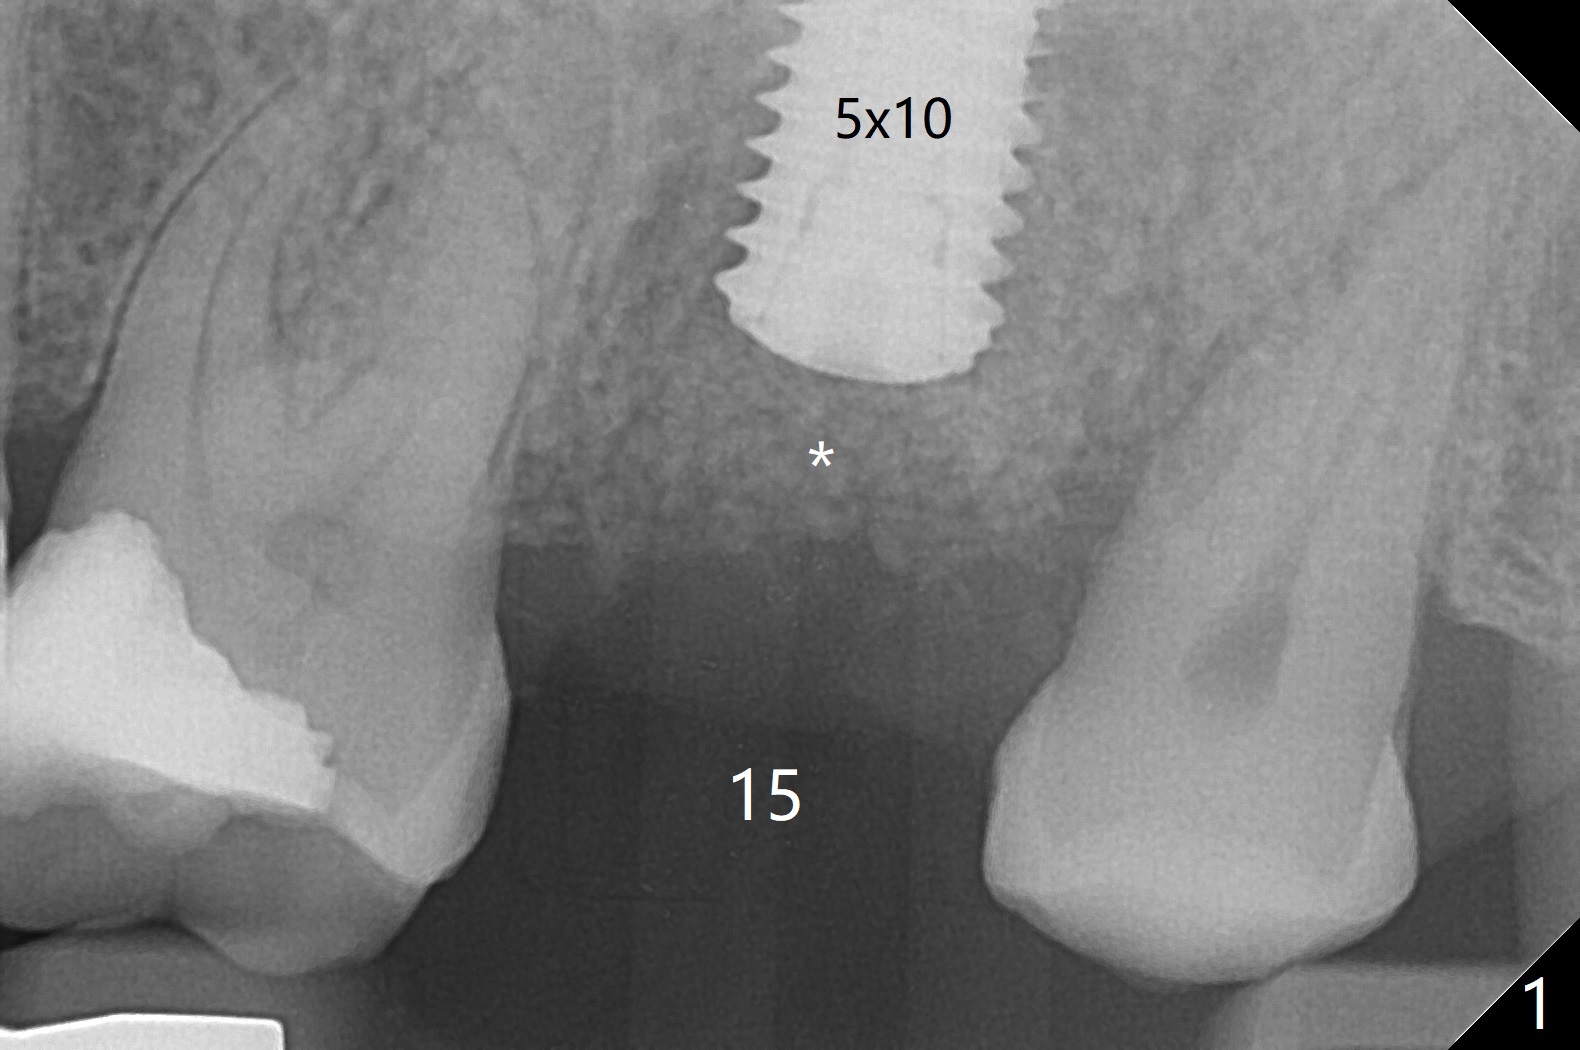

The longest (12 mm) bone trimmer seems not to work over the guide at #15.  When osteotomy finishes, the guide is removed.  The sinus floor happens to have been removed, whereas the sinus membrane remains intact.  After partial insertion of a piece of PRF membrane (due to hemorrhage) and Vanilla graft for sinus lift, a 5x10 mm implant is placed with 15 Ncm.  The implant appears to be short and placed deep (Fig.1,2).  When an implant is not too large, it can be placed ~ 1 mm subcrestal (vs. 2-3 mm for this case) in spite of the palatal wall defect.  A cover screw is used, followed by allograft (Fig.1 *).  The latter is covered with another piece of PRF membrane, collagen membrane and periodontal dressing.扭力有时是假象,如果植体卡在硬点(例如骨皮质)而产生高扭力之后骨坏死,植体可能松动。